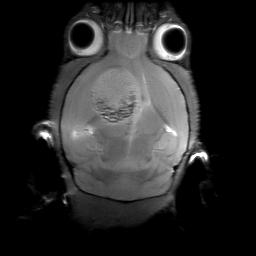

Image IRM d'une tumeur au cerveau